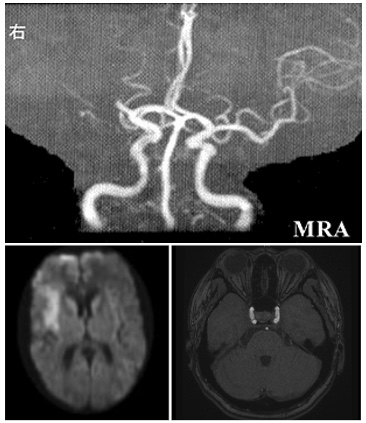

2022 B3 72歳男性 高血圧、脂質異常症あり。一過性構音障害を発症したため受診され、来院時のMRIで FLAIR(図1)、MRA(図2)、CISS(図3)の所見を認めた。 これらの所見より、適切な病態を一つ選びなさい。 図1:Axial のFLAIRが2枚あり、左PCA領域の高信号、両側深部白質の高信号を認めました。左後頭葉の梗塞部位はもう少し外側だったと思います。 図2:頭蓋内MRA 両側の前方循環は全く描出されておらず、後方循環、両側ECAのみ描出。ECAやPcomからの側副路も明らかな描出なし。左PCAは右と比較し、狭窄を認めました。(実際には→はありません) 図3:CISS coronal sagittal sylvius裂が見える断面。MCAproximal の血管外径狭小化を認める。

もやもや病